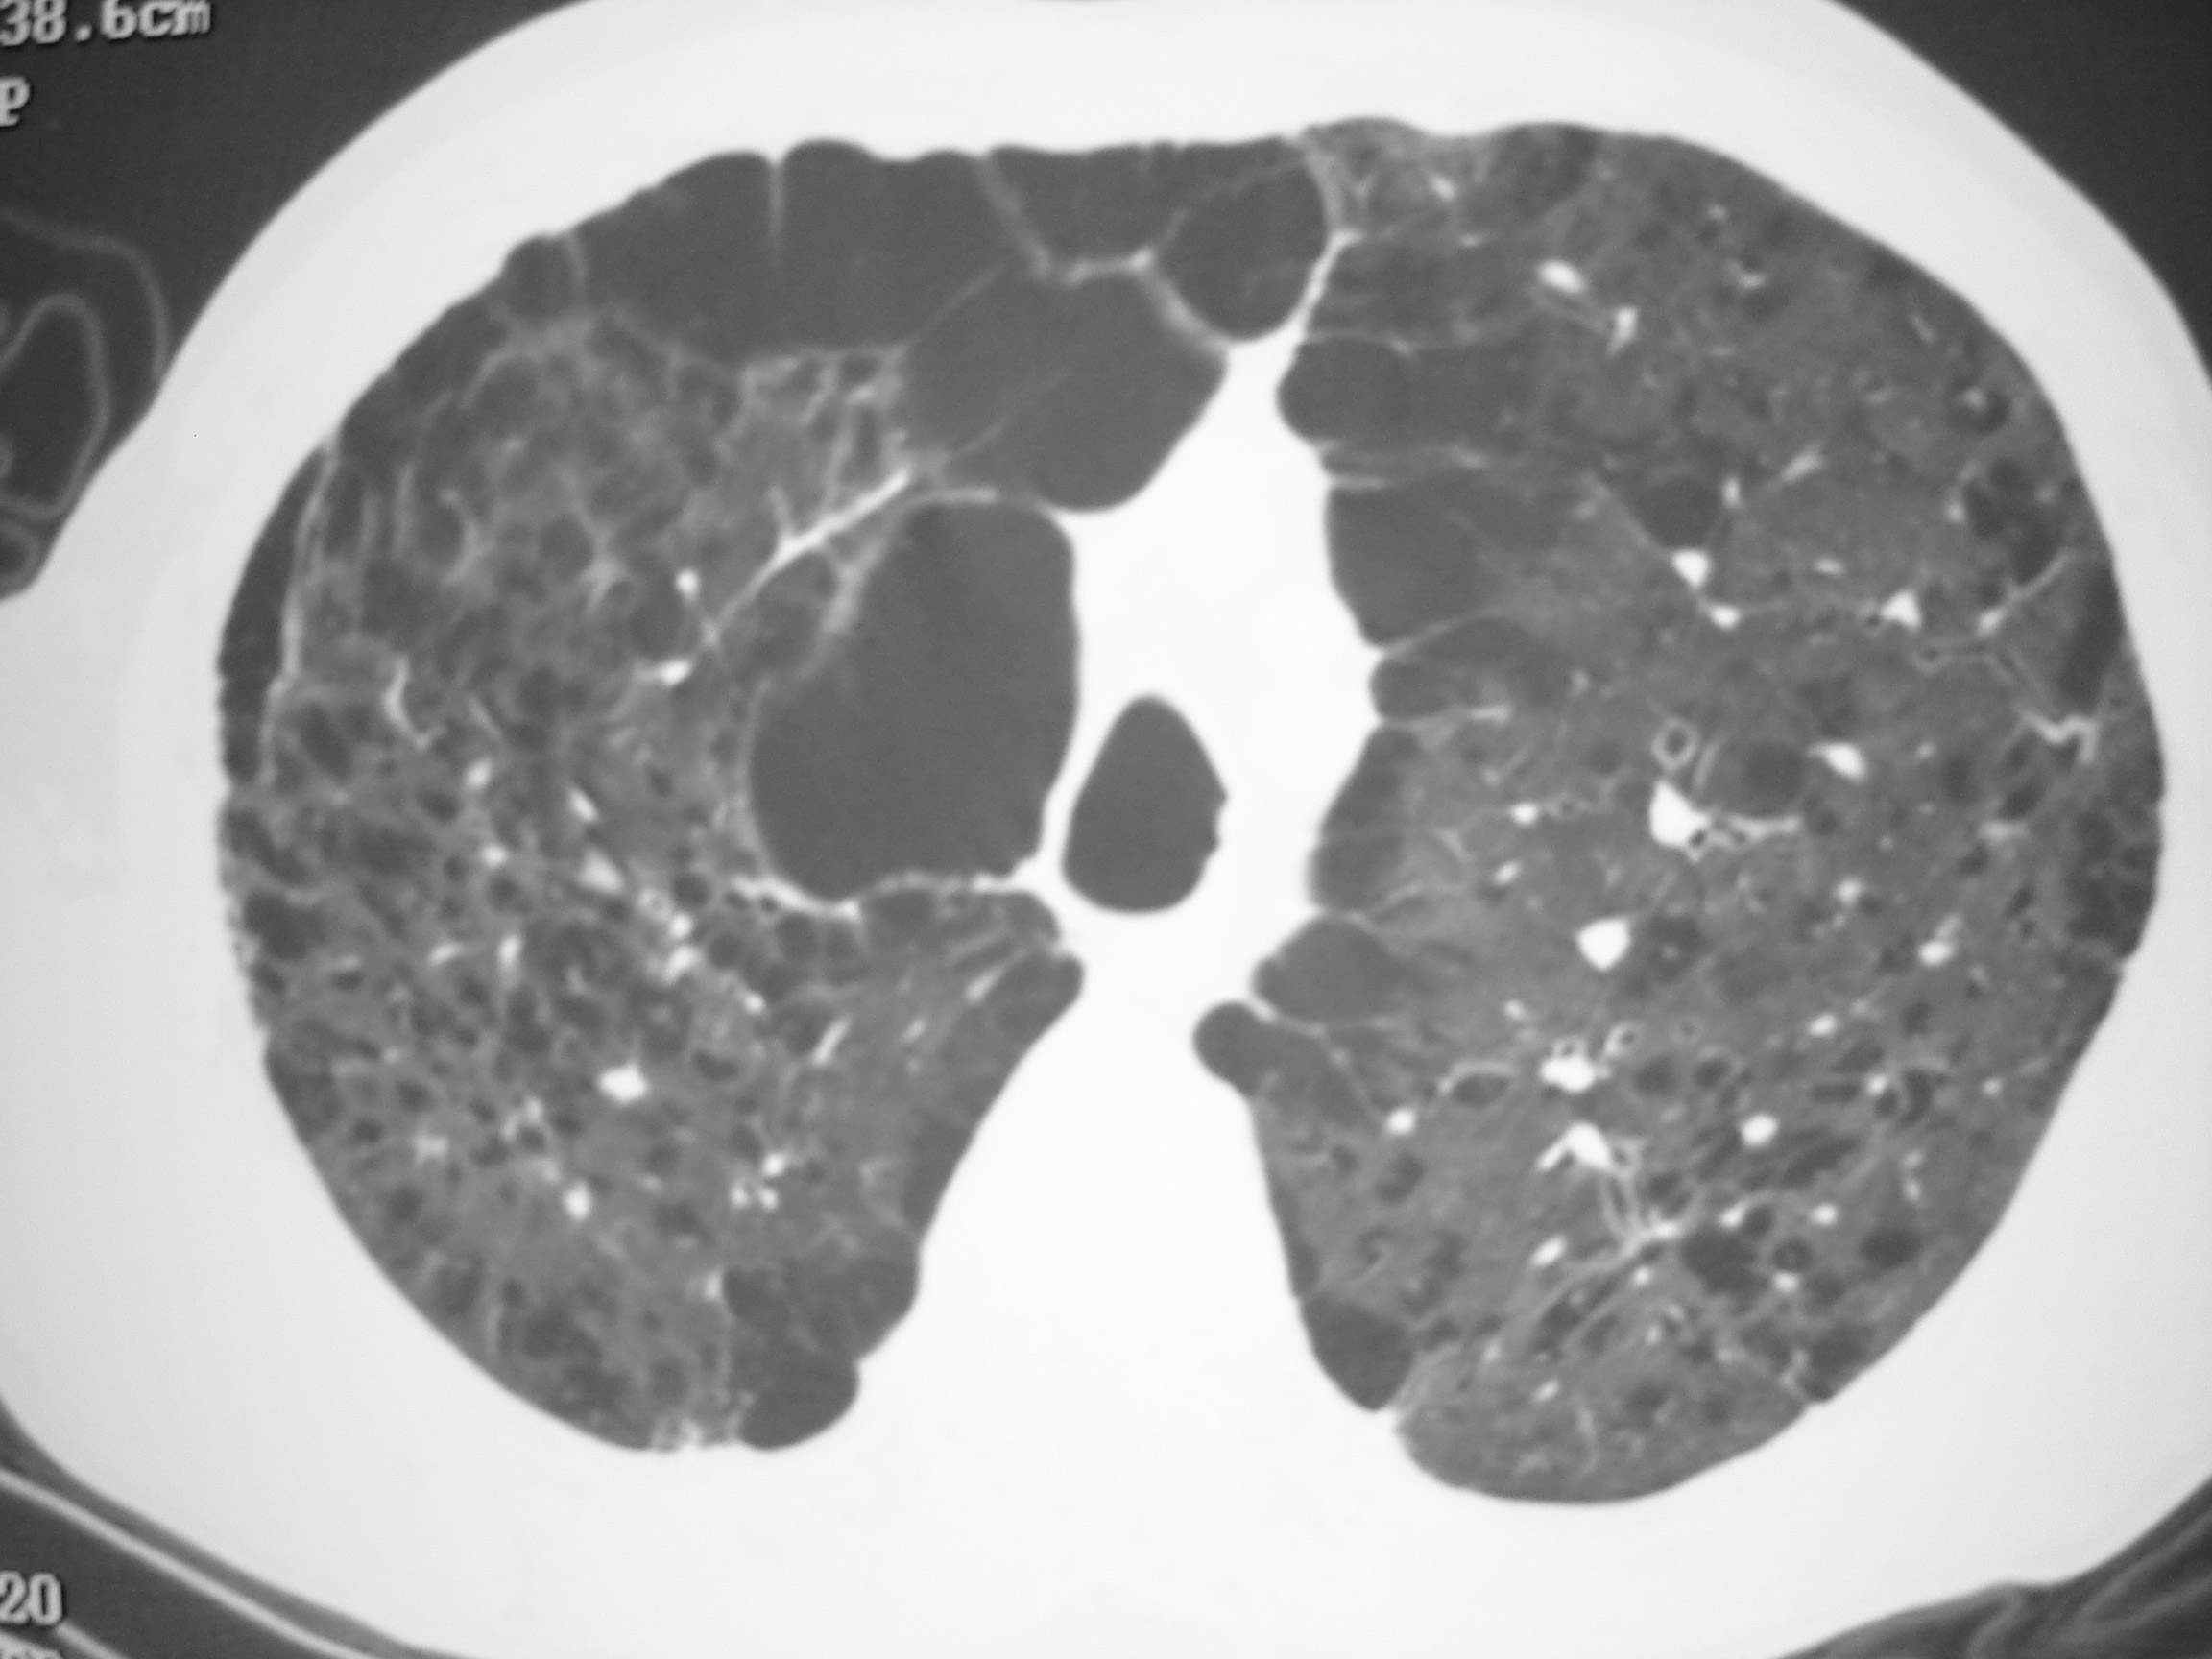

O enfisema pulmonar é a destruição do parênquima pulmonar, acarretando a perda da retração elástica dos septos alveolares e da tração radial das vias respiratórias, o que aumenta a tendência ao colapso destas. É sucedido por hiperinsuflação pulmonar, limitação do fluxo aéreo e aprisionamento de ar. Os espaços aéreos dilatam-se e com o tempo desenvolvem vesículas ou bolhas.